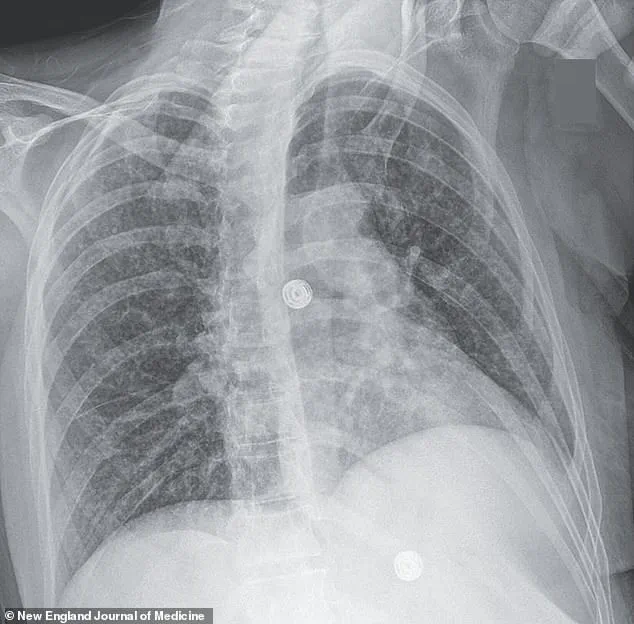

Initial X-ray scans of her lungs revealed small nodules, an abnormality often associated with bacterial infections.

Further imaging uncovered lesions in her liver, lymph nodes, pancreas, and brain—findings that pointed to a systemic infection.

The woman in the report had nodules detected in multiple organs, including her lungs, lymph nodes, liver, pancreas, and brain, as revealed by medical imaging.